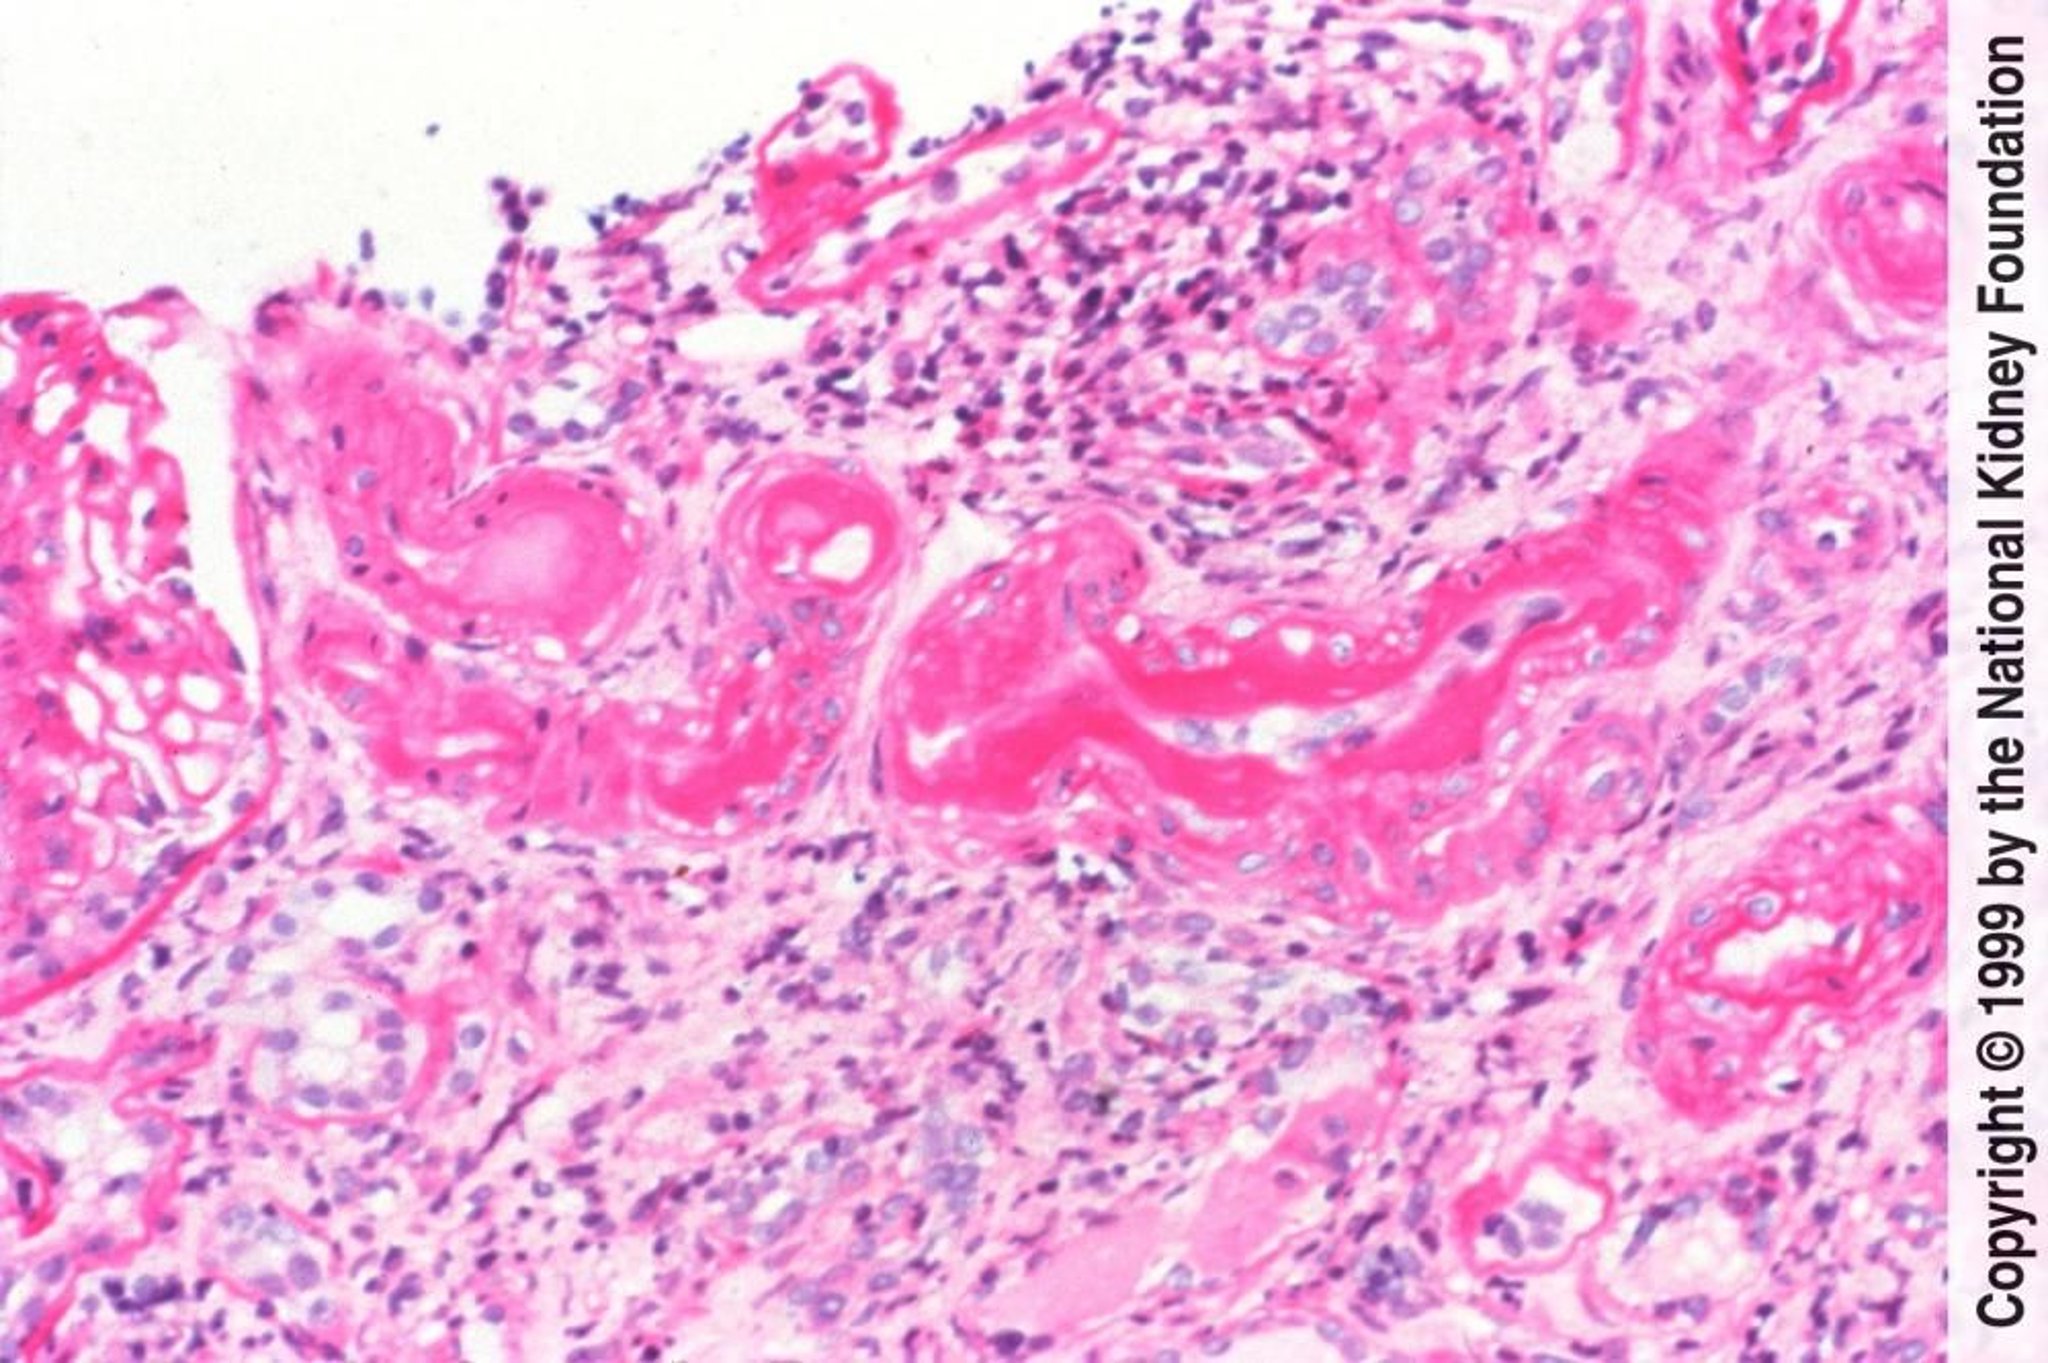

Nefroesclerosis arteriolar hipertensiva benigna

La nefroesclerosis arteriolar hipertensiva benigna se caracteriza histológicamente por hialinosis arteriolar causada por insudación de proteínas plasmáticas y engrosamiento medial causado por hipertrofia e hiperplasia de las células del músculo liso vascular (tinción de ácido peryódico de Schiff, × 200).

Image provided by Agnes Fogo, MD, and the American Journal of Kidney Diseases' Atlas of Renal Pathology (véase www.ajkd.org).